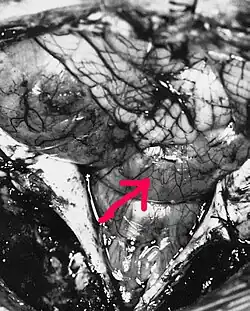

Эпендимомы головного мозга чаще располагаются внутри желудочковой системы, реже отмечается паравентрикулярная локализация этих опухолей. Эпендимомы спинного мозга растут интрамедуллярно (внутри спинного мозга), а развивающиеся из эпендимы терминального желудочка или терминальной нити — экстрамедуллярно (вне спинного мозга). Макроскопически опухоль имеет вид чётко отграниченного узла, в котором на разрезе могут определяться крупные гладкостенные кисты. В зоне исходного роста, как правило, отсутствуют чёткие границы с тканью мозга[2].